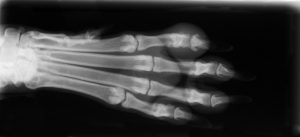

At Ark Veterinary Hospital in Kerrville, TX, we are proud to be on the cutting edge of medical technology. Radiology is a technique and diagnostic tool that we use to look inside the body in a completely non-invasive way. X-rays allow us to create images of all the body’s organs.

In other words, the use of radiology gives us a view of the internal organs in your pet’s body that we otherwise could not see. It’s an important diagnostic tool that helps veterinarians detect and prevent illness.